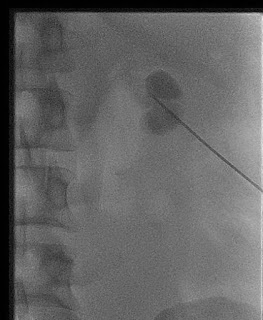

Two common techniques exist. The choice of technique depends on both operator and patient factors. One method utilizes a two- or three-part puncture needle and the other a micro-puncture kit. Using an aseptic technique and following infiltration of a local anaesthetic agent, the calyx (usually posterior calyx at the mid or lower pole) is punctured with an 18-gauge, two-part needle under ultrasound guidance. In the presence of renal tract obstruction, urine drains freely on the removal of the stylet from the needle.

A small volume

of water-soluble contrast

material can be injected to confirm the correct needle position using fluoroscopy. A 0.035 guide

wire is used to exchange

the needle for a dilator and

typically an 8 French pigtail drain is placed within the renal pelvis over the guide wire. On occasion,